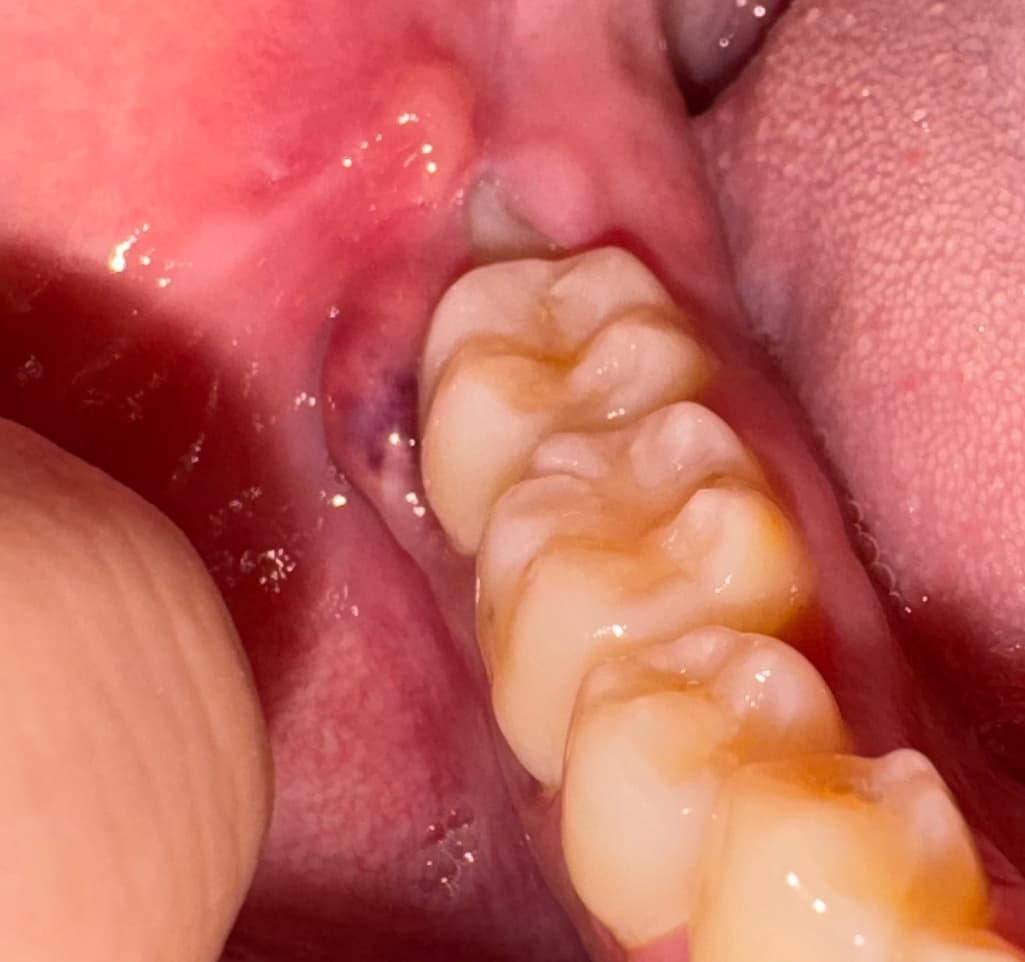

사진과 같이 어금니 오른쪽 잇몸이 붓고 보라색으로 출혈? 비슷하게 보이는게 있습니다. 어떤 증상인지, 심각한 문제인지 궁금합니다. 그리고 제가 현재 해외에서 유학 중이라서 바로 치과를 가는게 힘든 상황인데, 현지 치과라도 가야할 정도일지 궁금합니다.

사진으로 봤을 경우에는 사랑니가 천천히 올라오고 있는 것으로 보입니다. 사랑니가 부분적으로 올라와 있게 되면 해당 부위에 이물질이 끼게 되어 염증이 쉽게 생길 수 있습니다. 사랑니가 똑바로 나오고 문제가 없을 것이라 생각한다면 관리를 하면서 사용할 수도 있지만 지속적으로 음식물이 끼거나 염증으로 인해서 주변 조직에 손상이 있을 수 있다면 발치를 해주는 것이 좋습니다.

매복 사랑니 주위로 염증이 있어보이고, 그 앞 어금니 주변 잇몸도 염증이 있어보입니다. 적극적인 치과치료가 어렵다면 적어도 항생제 약 처방 정도는 받으시기 바랍니다.